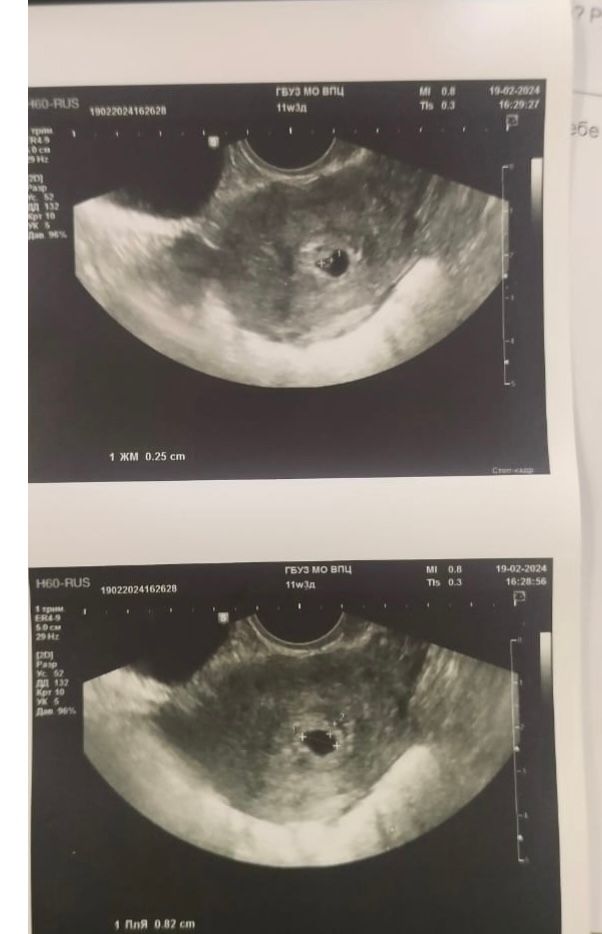

На той неделе как-то у неё болела грудь она сделала тест тест ничего не показал через день тест показал две полоски, сходила к врачу сделали узи.

пришла сегодня к врачу по узи плодное яйцо выросло .

Хгч растёт, есть только пару вариантов , либо болезнь, либо беременность. Т.к на узи были уже видно что беременность формируется, у меня такой снимок узи был в 6-7 недель беременности